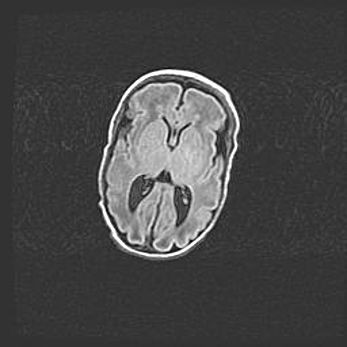

Лейкомаляция с кистозно-глиозной дегенерацией головного мозга.

Возраст: 2 месяца 25 дней

Вес: 6400 г

Окружность головы: 40 см

Срок гестации: 41 неделя

Лейкомаляцию относят к ишемически-гипоксическим повреждениям головного мозга, диагностируемым у новорожденных. При лейкомаляции в головном мозге обнаруживают очаги некроза, возникшие после тяжелой гипоксии и нарушения кровотока. В процессе морфогенеза очаги проходят три стадии: 1) развития некроза, 2) резорбции и 3) формирования глиозного рубца или кисты. Перивентрикулярная лейкомаляция (ПЛ) встречается примерно в 12% случаев среди новорожденных, обычно – у недоношенных детей, причем, частота ее зависит от массы, с которой младенец появился на свет. Наибольшее число малышей страдает лейкомаляцией, если масса при рождении 1500-2500 г.